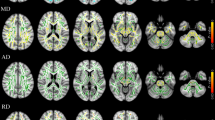

Diffusion tensor Imaging of cerebellar peduncles

Compared to HS, early PD patients exhibited lower FA and higher MD and RD values in all three cerebellar peduncles. Early PD patients also exhibited higher AD values in MCP and SCP (Fig. 2, Table 3).

The figure depicts axial diffusivity (AD), fractional anisotropy (FA), mean diffusivity (MD), and radial diffusivity (RD) alterations between early PD patients and HS within three cerebellar tracts: inferior cerebellar peduncle (ICP), middle cerebellar peduncle (MCP), and superior cerebellar peduncle (SCP). The early PD group was indicated by the yellow color and the HS one was indicated by the blue color. The median marks the data’s midpoint and is shown by the red line. The upper and lower whiskers represent the 75th and 25th percentiles, respectively. The whiskers extend to the most extreme data points not considered outliers, and the outliers are plotted individually using the “+” symbol.